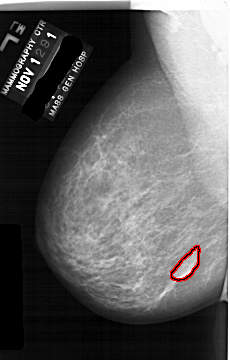

A_1691_1.LEFT_CC

LEFT_CC LINES 6871 PIXELS_PER_LINE 3946 BITS_PER_PIXEL 12 RESOLUTION 43.5 OVERLAY

FILE: A_1691_1.LEFT_CC.OVERLAY

TOTAL_ABNORMALITIES 1

ABNORMALITY 1

LESION_TYPE MASS SHAPE LOBULATED MARGINS CIRCUMSCRIBED

ASSESSMENT 4

SUBTLETY 4

PATHOLOGY BENIGN

TOTAL_OUTLINES 1

BOUNDARY